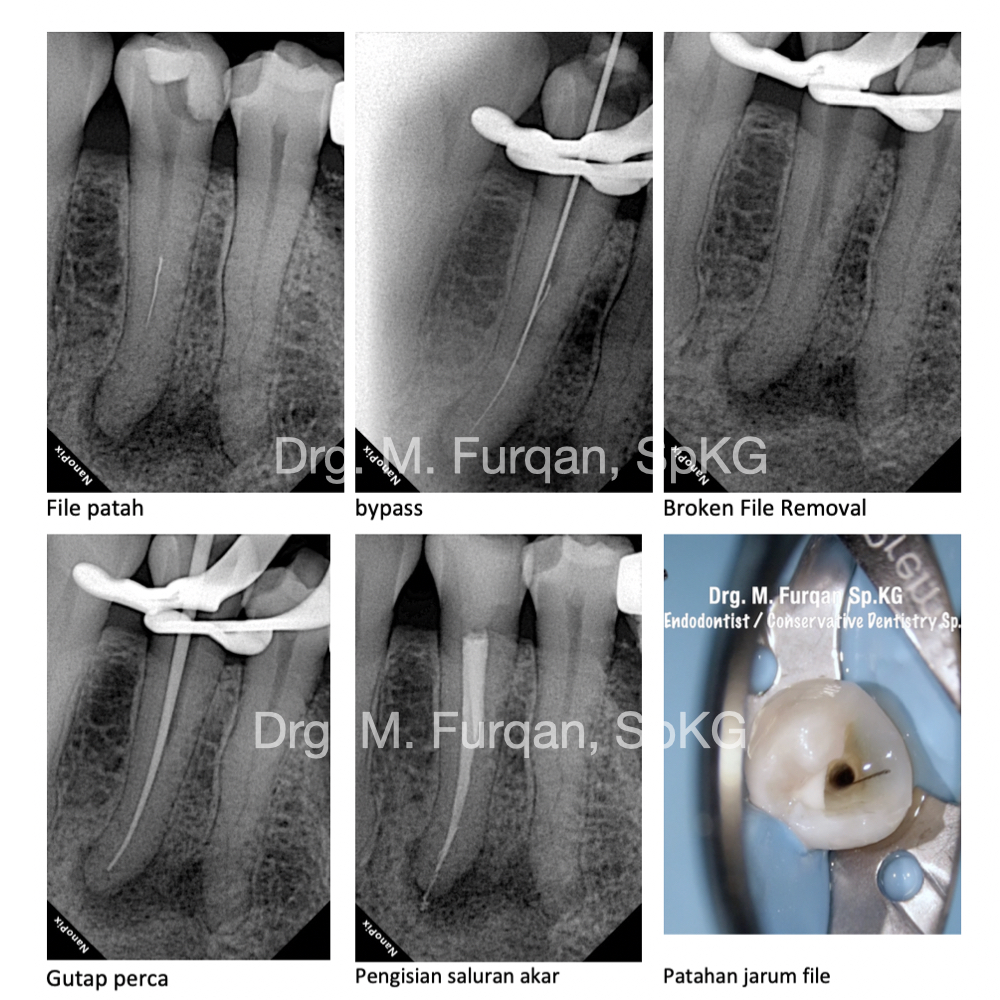

Perawatan saluran akar adalah salah satu perawatan yang berfungsi untuk menghilangkan atau memberhentikan sumber infeksi yang berkembang biak. Sering kali perawatan ini di sebut dengan perawatan saraf atau perawatan syaraf gigi, penggunaan nomenklatur ini dirasa kurang tepat. Tujuan lain dari perawatan saluran akar selain menghilangkan infeksi, perawatan saluran akar bertujuan mempertahankan gigi semaksimal mungkin didalam rongga mulut. Root Canal Treatment or Root Canal Therapy are The process of removing an infected, inflamed, or necrotic pulp and filling the residual space with an inert material. Access must first be gained to the pulp chamber and root canal system; the pulp canals are then measured and the pulp tissue and any infected material removed; the canals are then shaped, irrigated, and cleaned of debris; the root canals are obturated with a root filling material such as gutta-percha and a sealant, and finally a coronal seal placed to prevent bacteria from the mouth entering the root canal system. thank you for eighteeth dental and revoden asia using fast fill and fast pack to fiilling a root canals for more info you can visit my instagram https://www.instagram.com/furqan_rizal/ or contact my clinic +6281219972701